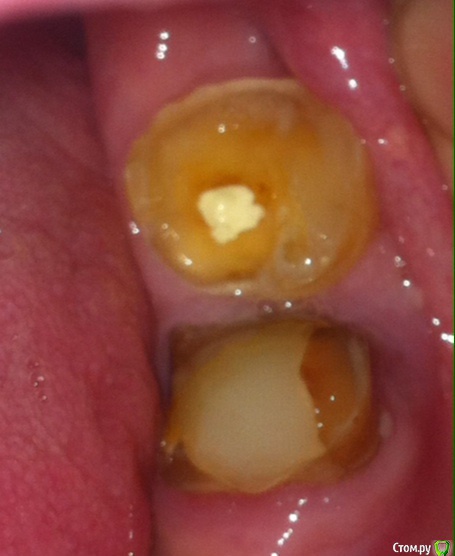

Получил предложение восстановить зуб с помощью Эстелайт + SDR. Возможно ли это для раскрошившегося зуба, у которого остались только 60% стенок и край скола на уровне десны. Зуб планируется использовать для крепления ЧСП.

Речь про верхний на фото зуб - 38